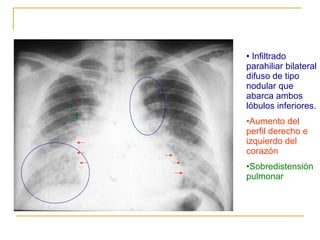

Infiltrado parahiliar bilateral difuso de tipo nodular que abarca ambos lóbulos inferiores. Aumento del perfil derecho e izquierdo del corazón Sobredistensión pulmonar

Infiltrado parahiliar bilateraldifuso de tipo nodular que abarca ambos lóbulos inferiores. Aumento del perfil derecho e izquierdo del corazón Sobredistensión pulmonar